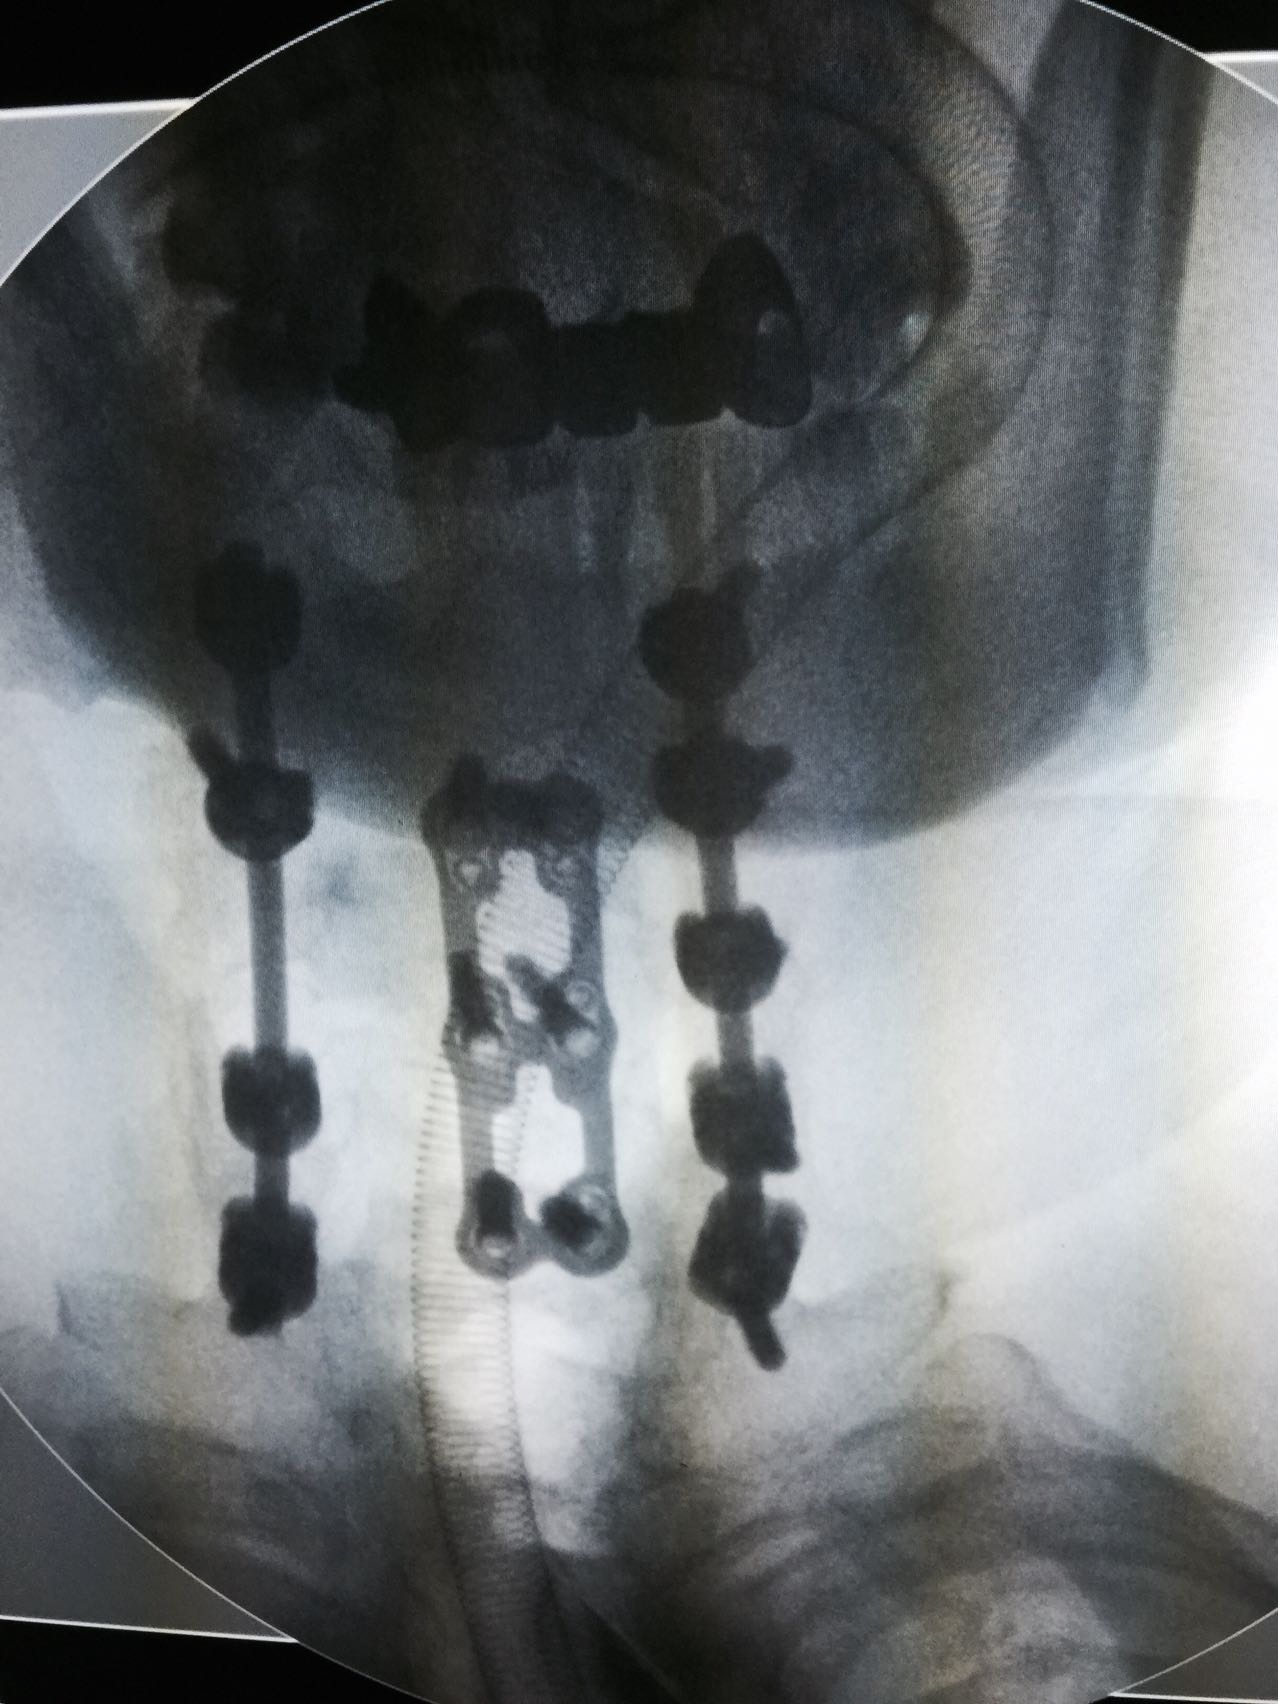

强直性脊柱炎并C5骨折 四肢瘫痪